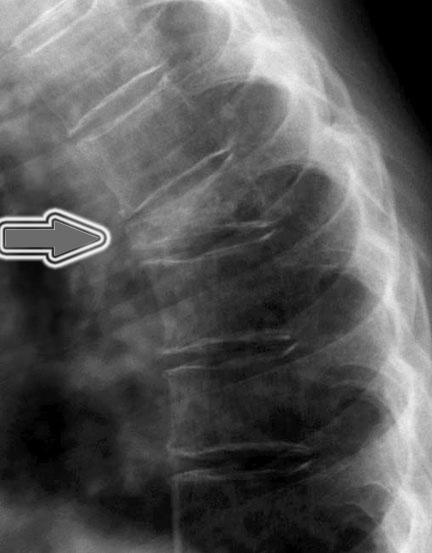

Nel sospetto di una frattura vertebrale viene eseguita una radiografia della colonna (Fig. 5). Se il sospetto clinico viene confermato si approfondisce la diagnostica ricorrendo alla Risonanza Magnetica (Fig. 6) che fornisce informazioni sul “timing” : cioè se la frattura è recente o di vecchia data.

Fig. 5 La freccia indica la vertebra osteoporotica fratturata in un esame RX